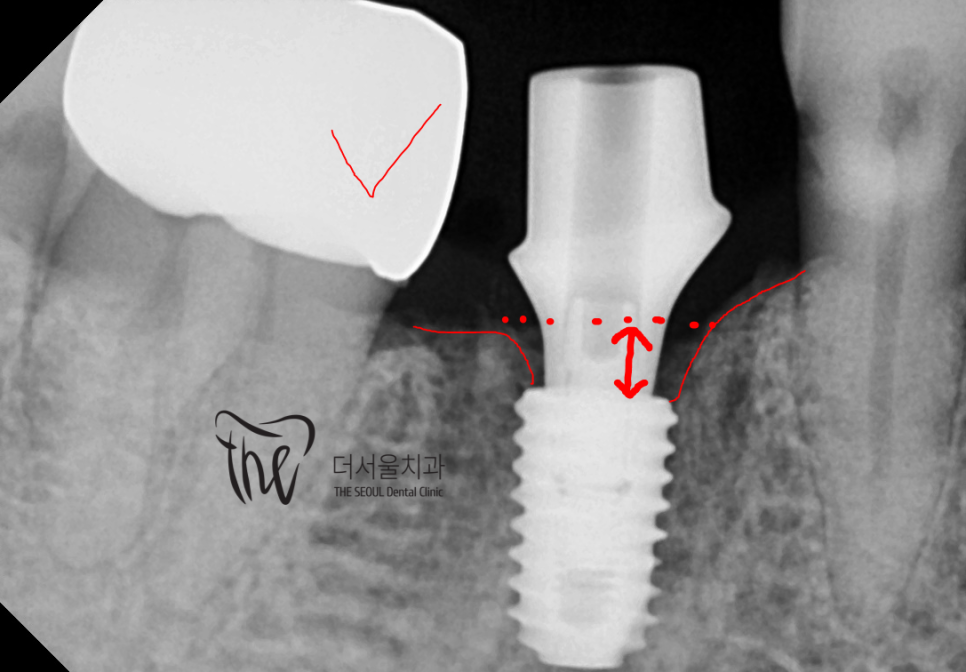

디지털 임플린트 진단에 따라서

Bone level 하방 2mm 가량 되는 위치에

implant fixture 를 심어드렸습니다.

어금니에 위치되는 곳이기 때문에,

본래 어금니 만큼의 높은 교합력을 내면서

오래 유지를 시켜드리려 이렇게 심어드렸었죠.